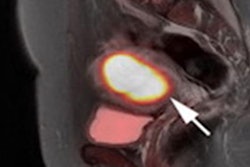

Hybrid PET/MRI is a new frontier for breast imaging, as it allows a comprehensive tumor assessment, from morphology to functional properties, according to research shown at ECR 2022 in Vienna.

A team from the University of Naples in Italy led by Dr. Valeria Romeo, PhD, compared F-18 FDG PET/MRI and diffusion-weighted (DWI) MRI for diagnosing breast cancer diagnosis. They found that while the addition of PET did not significantly improve the accuracy of MRI, it did identify additional lesions during staging and reduced the need for biopsies.

"PET/MRI shares basically the same clinical indication as PET/CT with the possibility to also be employed for performing local tumor staging due to its superb contrast resolution over breast tissue," Romeo said.

MRI is used routinely in patients with newly diagnosed breast cancer to assess the local extent of disease and assist in surgical and treatment planning, yet it can produce inconsistent results. PET/MRI has shown promise as an alternative approach in early studies, but the contribution of PET to MRI remains undefined due to limited experience with hybrid scanners and conflicting findings, according to Romeo.